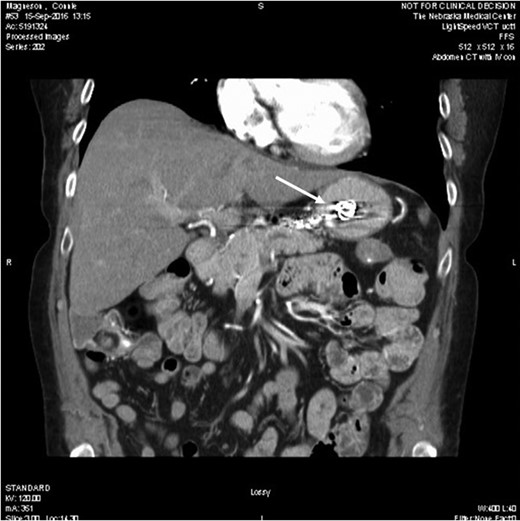

A 65 -year-old woman with a known history of multiple splenic and hepatic aneurysms was admitted to our hospital in October 2012 with acute abdomen. Abdominal computed tomography angiography showed rupture of splenic aneurysm with active extravasation of contrast and associated large left upper quadrant hematoma with small hemoperitoneum (Fig. 1). Visceral angiogram confirmed the presence of three fusiform aneurysms involving midsplenic artery (Fig. 2). The distal most aneurysm demonstrated large extravasation (Fig. 3). Coil embolization of the proximal and midsplenic artery aneurysm was performed using multiple Nester coils (Cook Medical, USA) with cessation of antegrade flow (Fig. 4). Attempt to access distal portion of the splenic artery was unsuccessful. She recovered well and was discharged 4 days later. In December 2016, she was admitted with dyspepsia and severe iron deficiency anemia requiring blood transfusion. A colonoscopy and upper endoscopy were performed which showed the presence of metallic coils in the stomach (Fig. 5). The patient subsequently underwent a combined upper endoscopy and laparoscopy. Three 5 mm ports were used to expose the lesser sac in event of hemorrhage during extraction of the coil endoscopically. An atraumatic bowel clamp was placed distal to the Treitz ligament to prevent insufflation of the small bowel. Upper endoscopy was performed using CO2 insufflation and the Nester coils were retrieved using rat tooth forceps (Fig. 6). There was no bleeding in the lesser sac after removal of the coils. A leak test was performed to rule out gastric perforation. She had an uneventful recovery and was discharged the next day.

Computed tomography showed three saccular splenic artery aneurysms with a large left upper quadrant hematoma (block white arrow) and blush from distal splenic aneurysm.